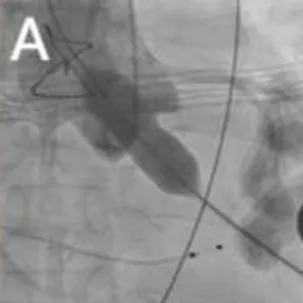

2025年6月4日,在全身麻醉下,通过TEE和荧光镜引导进行手术。通过右颈内静脉建立临时起搏。经左前外侧小切口暴露第五肋间隙,使用双重荷包缝合固定心尖;静脉注射肝素使活化凝血时间(ACT)>250秒。心尖穿刺后,先使用软导丝穿过主动脉瓣口,随后更换为Amplatz超硬导丝(波士顿科学公司)。在快速起搏(180次/分)下,使用18mm球囊对主动脉瓣生物假体进行预扩张。选择21mm ScienCrown瓣膜,旋转手柄将瓣膜从输送系统中逐步释放(视频1)。瓣膜成功植入后,无错位或瓣周漏(PVL)(图2B及视频2)。TEE显示主动脉瓣平均跨瓣压差为6mmHg,无瓣周漏(图2C及D)。随后,使用硬导丝穿过二尖瓣生物瓣进入左心房(视频3)。在快速起搏(180次/分)下于二尖瓣位置植入25mm ScienCrown瓣膜(图2E及视频4)。TEE显示二尖瓣平均跨瓣压差为5mmHg,瓣叶运动正常,无瓣周漏(图2F)。术后荧光检查显示两枚瓣膜均位置良好(图2G)。术后第一天床旁TTE显示二尖瓣压差2.52mmHg,流速0.76m/s;主动脉瓣压差13.39mmHg,流速1.7m/s,提示轻度主动脉瓣狭窄(AS)和正常二尖瓣功能(图3)。患者心功能改善至NYHA II级,并在术后第5天出院。

图2. 使用ScienCrown瓣膜进行经心尖主动脉瓣和二尖瓣ViV手术。A:18mm球囊对主动脉瓣进行预扩张。B:成功植入21mm ScienCrown瓣膜,显示无瓣周漏。C:植入后TEE确认无瓣周漏。D:术后TEE记录主动脉瓣平均跨瓣压差为6mmHg。E:二尖瓣位置25mm ScienCrown瓣膜的理想释放。F:植入后TEE评估显示二尖瓣平均跨瓣压差为5mmHg。G:术后影像学检查显示两枚植入假体瓣膜的位置及形态均正常。